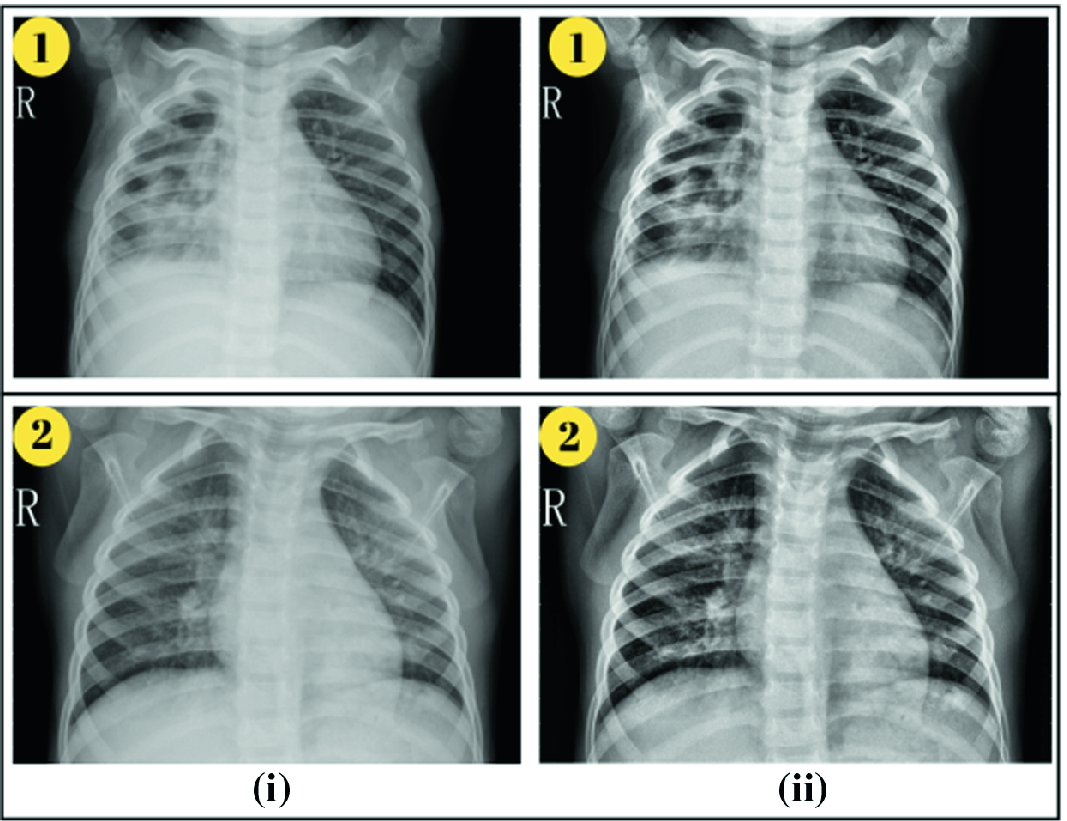

Deep Convolutional Neural Network With Transfer Learning For Detecting Pneumonia On Chest X Rays Springerlink from media.springernature.com Often, people with recurrent bouts of pneumonia tend to have unidentified lung cancer that can progress to advanced stages without appropriate treatment. A white spot amidst the normal black lungs can therefore be a cancer, infection. Here's why cancer can look like an infection: Persistent chest infections can be signs of something more serious than pneumonia, and unfortunately, it. A retrospective study of 1011 hospitalized patients with pneumonia was undertaken to assess the value of routine convalescent chest radiography for detection of underlying lung cancer. The first of these possibilities could be investigated by bronchoscopy. But the pneumonia density can obscure, or be distal to a cancer. Typical signs of bacterial pneumonia include fever, difficulty breathing, lethargy and coughing.